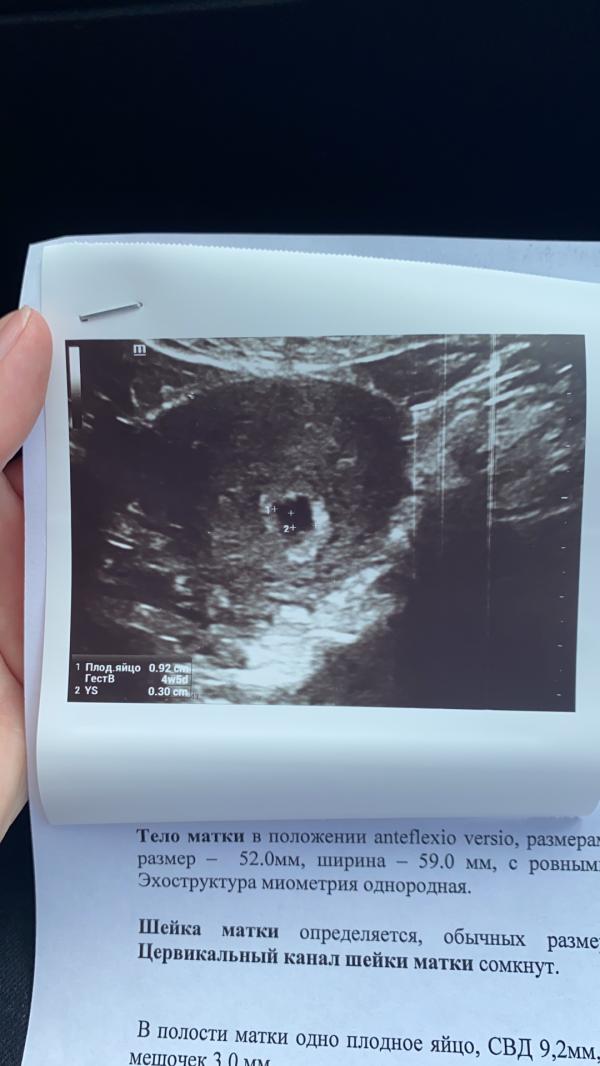

Узи хотели сделать вагинальную, я побоялась и отказала. Сделали на животе, зафиксировали беременность. Срок поставила 4 недели 5 дней.

Ну ниче увидела. Но состояние не смогла определить, так как срок маленький , а чтобы отпределить надо вагинально узи делать. Но я боюсь вагинальной, у многих же после такого коричневые выделения пишут. Нафиг мне это. Подожду до 1 скрининга лучше